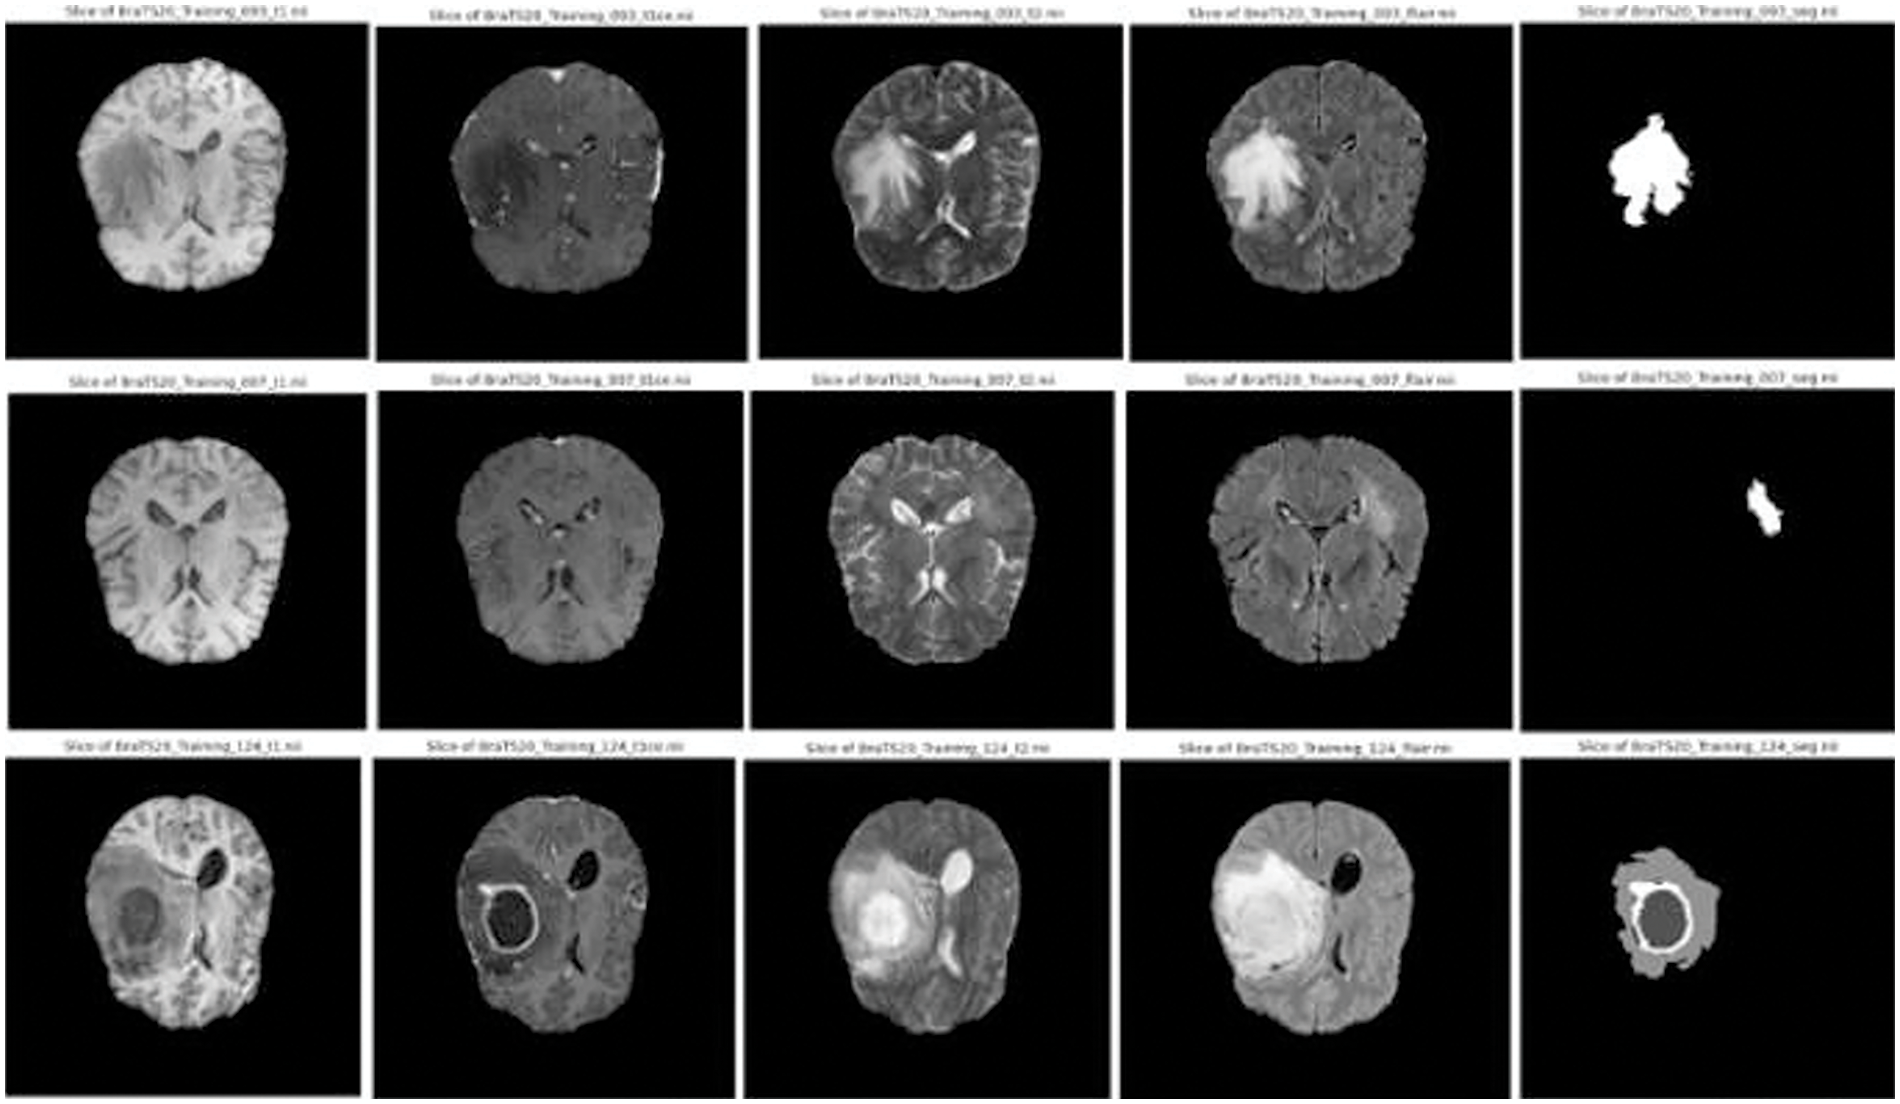

The BraTS (Multimodal Brain Tumor Segmentation Challenge) datasets, spanning 2018 to 2021, have become a cornerstone for glioma research. Each year offers a significant number of cases: 285 in 2018 [33], 335 in 2019 [34], 369 in 2020 [35], and 1251 in 2021 [36]. These cases encompass high-grade gliomas (HGG) and low-grade gliomas (LGG). Each case has four MRI modalities (T1, T1ce, T2, and FLAIR) and their respective masks with consistent dimensions (

Figure 3: Sample images and corresponding segmentation masks in brats’ dataset